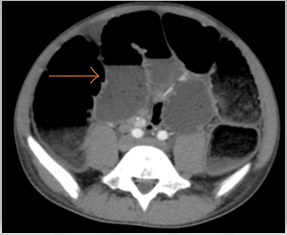

Nội soi đại trực tràng: Đèn soi đi đường hậu môn nhân tạo, ngay dưới hậu môn nhân tạo có khối sùi loét chiếm gần hết chu vi, phần đại trực tràng còn lại không thấy tổn thương.

Hình 2 Hình ảnh nội soi đại tràng